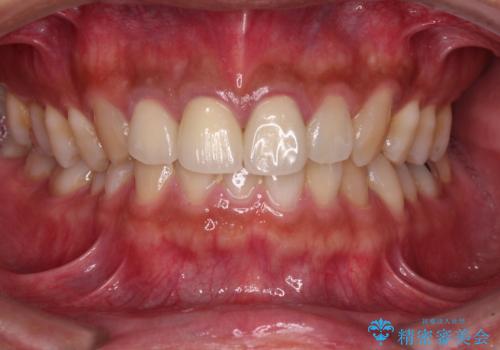

変色した歯はきれいになり、両隣の歯とも自然に馴染み、ご家族からも好評で大変満足されました。